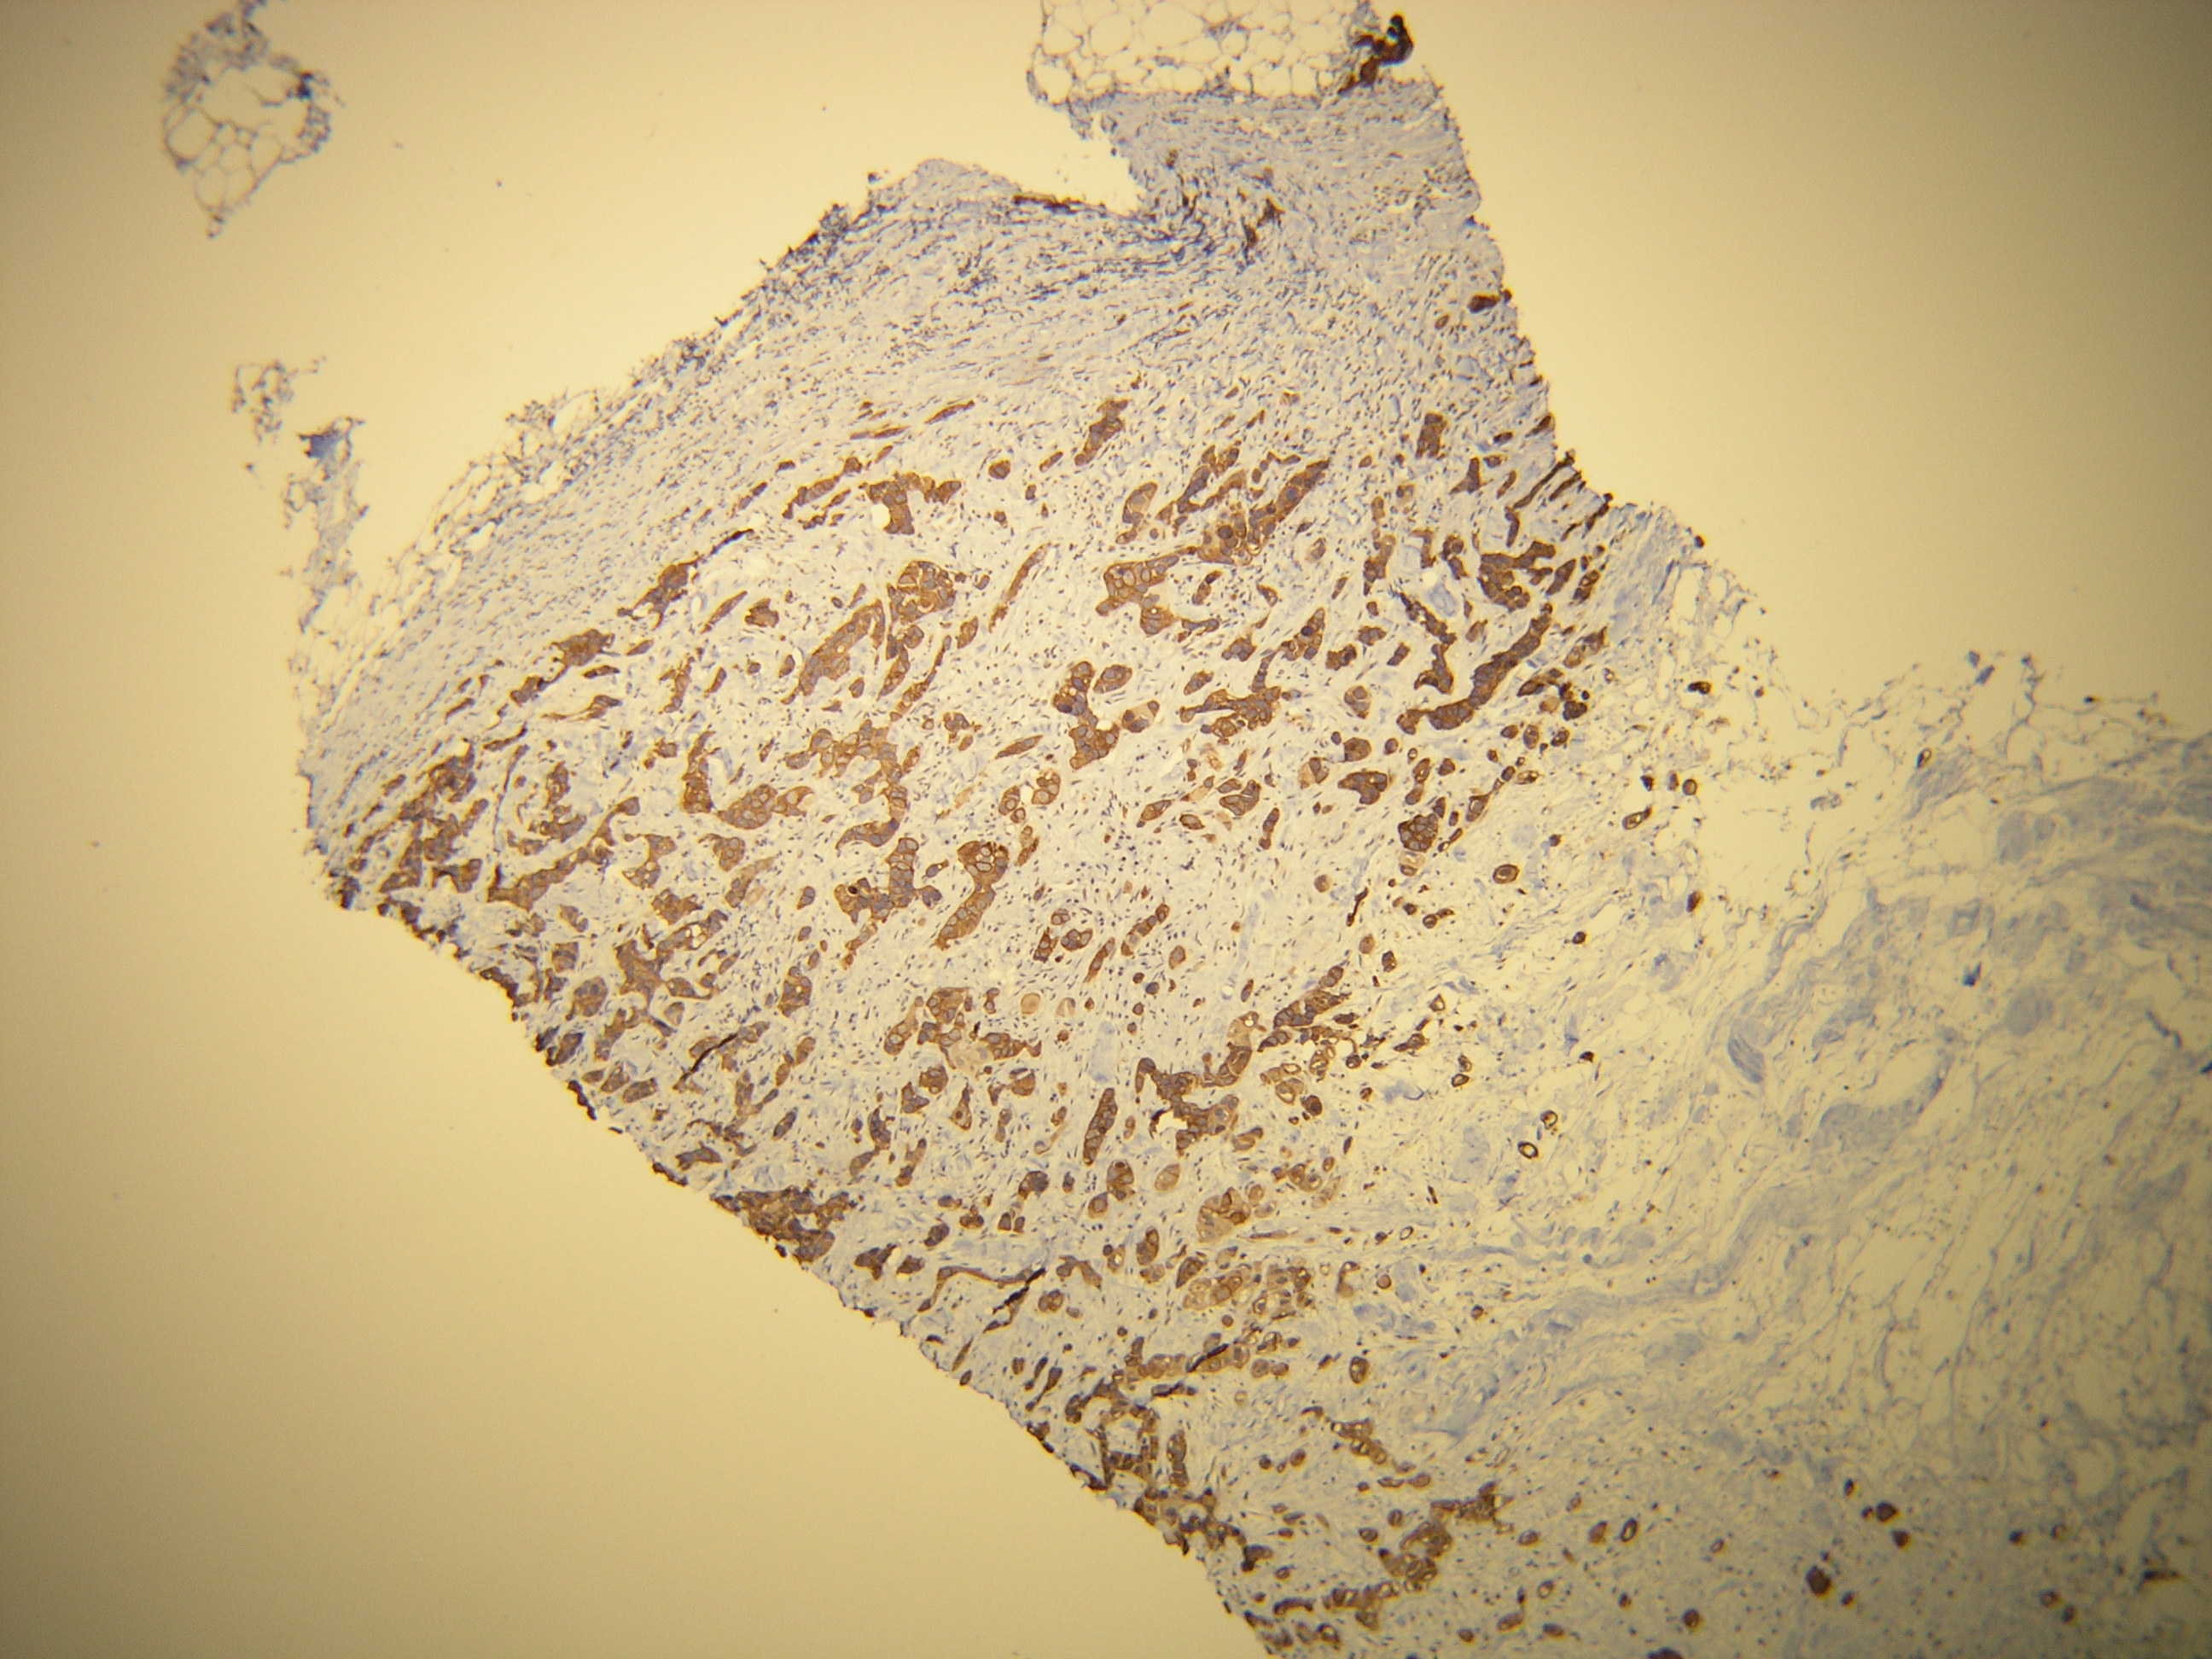

Anti-Cytokeratin 7

Peptid derivovaný z N-koncovej sekvencie ľudského cytokeratin 7. Protilátka rozpoznáva epitop umiestnený medzi Ala22 - Ser38.

Aplikácia

IHC-P, riedenie 1:100

db051 db051b db051c